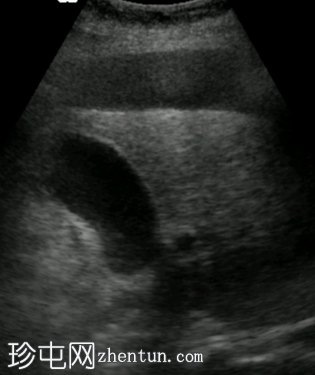

纵向

超声图像显示右上腹肝脏周围存在均匀的无回声区域。左上腹脾脏附近也存在类似的无回声区域,肠管之间的盆腔内也存在无回声区域。这些积液的总体积估计为3-4升。胆囊外观未见异常,无结石或壁增厚的迹象。由于上覆肠道气体和患者体型特征,胰腺肿块未能清晰显示。